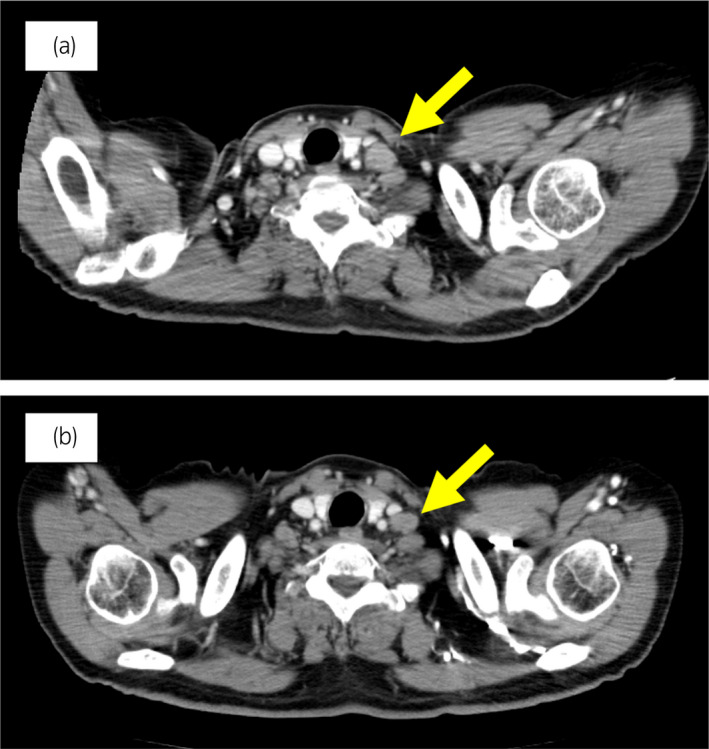

70 歲男性被診斷為轉(zhuǎn)移性 PC,cT3bN1M1b,Gleason 評分(GS)為 4 + 5 = 9,前列腺特異性抗原(PSA)水平為 40.8ng/ml,3 年前伴有胸椎轉(zhuǎn)移。 對前列腺進(jìn)行聯(lián)合雄激素阻斷 (CAB) 治療和質(zhì)子放射治療 (78.0Gy/39fr)。 PSA 水平降至 <0.01ng/ml,CAB 在 2.5 年后停止。 停止 CAB 五個月后,他出現(xiàn)背痛,PSA <0.01 ng/ml。 計算機(jī)斷層掃描 (CT) 掃描檢測到多處肝、骨和淋巴結(jié)轉(zhuǎn)移,神經(jīng)元特異性烯醇化酶 (NSE) 水平高達(dá) 171ng/ml(圖 1a)。 骨轉(zhuǎn)移活檢顯示神經(jīng)內(nèi)分泌前列腺癌 (NEPC) 的診斷(圖 2),患者被轉(zhuǎn)診至佳學(xué)基因合作醫(yī)院。 內(nèi)分泌腫瘤正確治療醫(yī)生用順鉑、依托泊苷和亮丙瑞林治療。 第三個療程后,轉(zhuǎn)移部位明顯縮?。▓D 1b)。 順鉑和依托泊苷治療 1 年,但患者因神經(jīng)病變要求停藥。 他開始服用恩雜魯胺。 治療 3 個月后,患者出現(xiàn)背痛和左鎖骨下淋巴結(jié)腫大(圖 3a)。 肝轉(zhuǎn)移保持不變,順鉑治療后縮小。 通過腫瘤正確用藥850基因檢測證實(shí)了 BRCA2 突變。根據(jù)基因檢測結(jié)果,主治腫瘤科醫(yī)生給予了奧拉帕尼。 三個月后,背痛好轉(zhuǎn),淋巴結(jié)轉(zhuǎn)移縮小,確定為部分緩解(PR)(圖3b)。 肝轉(zhuǎn)移灶保持不變。

圖 3:案例 1. 開始使用奧拉帕尼之前和之后 3個月的鎖骨下淋巴結(jié)轉(zhuǎn)移的 CT 圖像。 (a) 治療前和 (b) 奧拉帕尼治療后 3 個月。 黃色箭頭顯示轉(zhuǎn)移淋巴結(jié)。